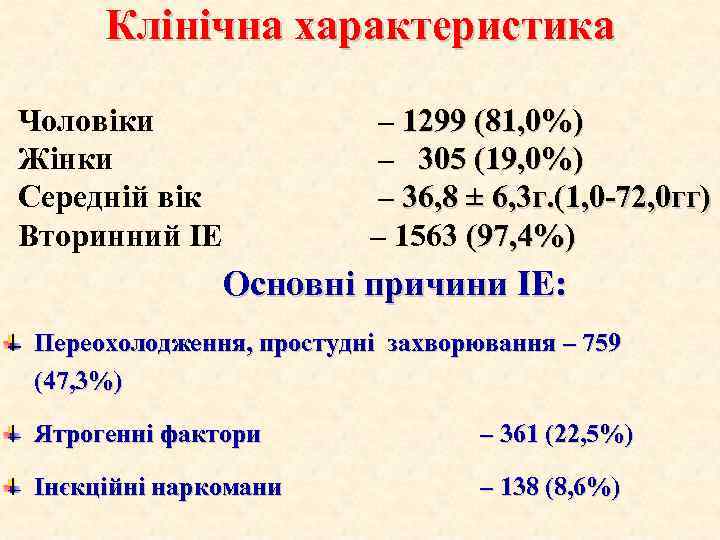

Клінічна характеристика Чоловіки Жінки Середній вік Вторинний ІЕ – 1299 (81, 0%) – 305 (19, 0%) – 36, 8 ± 6, 3 г. (1, 0 -72, 0 гг) – 1563 (97, 4%) Основні причини ІЕ: Переохолодження, простудні захворювання – 759 (47, 3%) Ятрогенні фактори – 361 (22, 5%) Інєкційні наркомани – 138 (8, 6%)